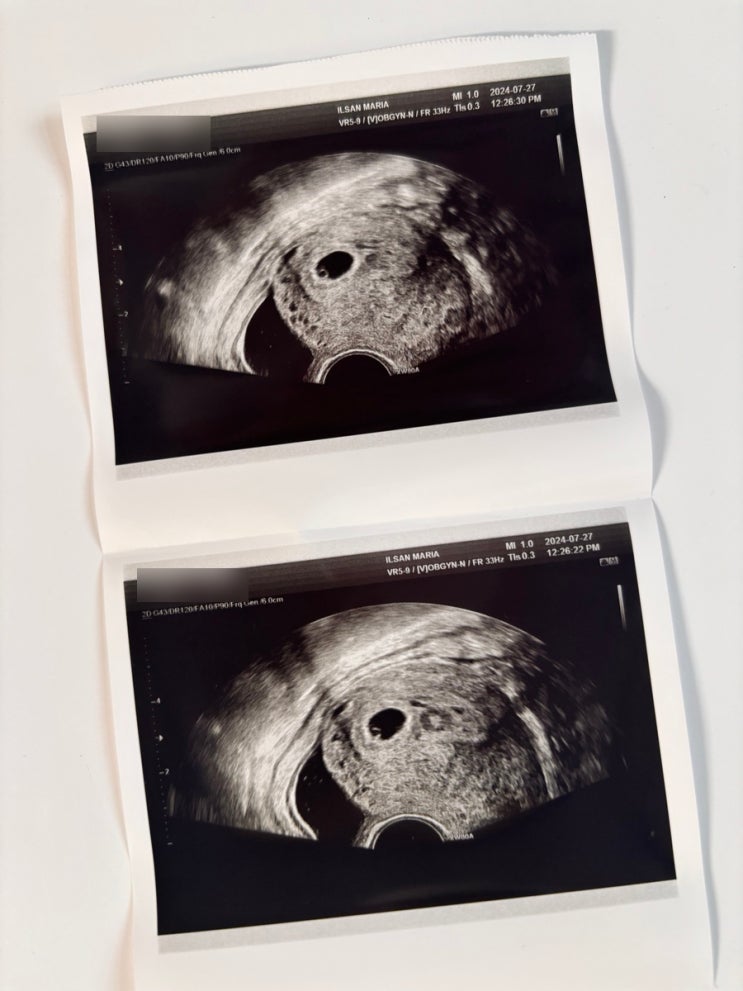

임신 6~8주 차 증상 및 태아 심장소리 초음파 영상

안녕하세요! 노링입니다 :) 오늘은 임신 6~8주차 증상과 태아 심장소리 초음파 영상을 공유해 보도록 할게...